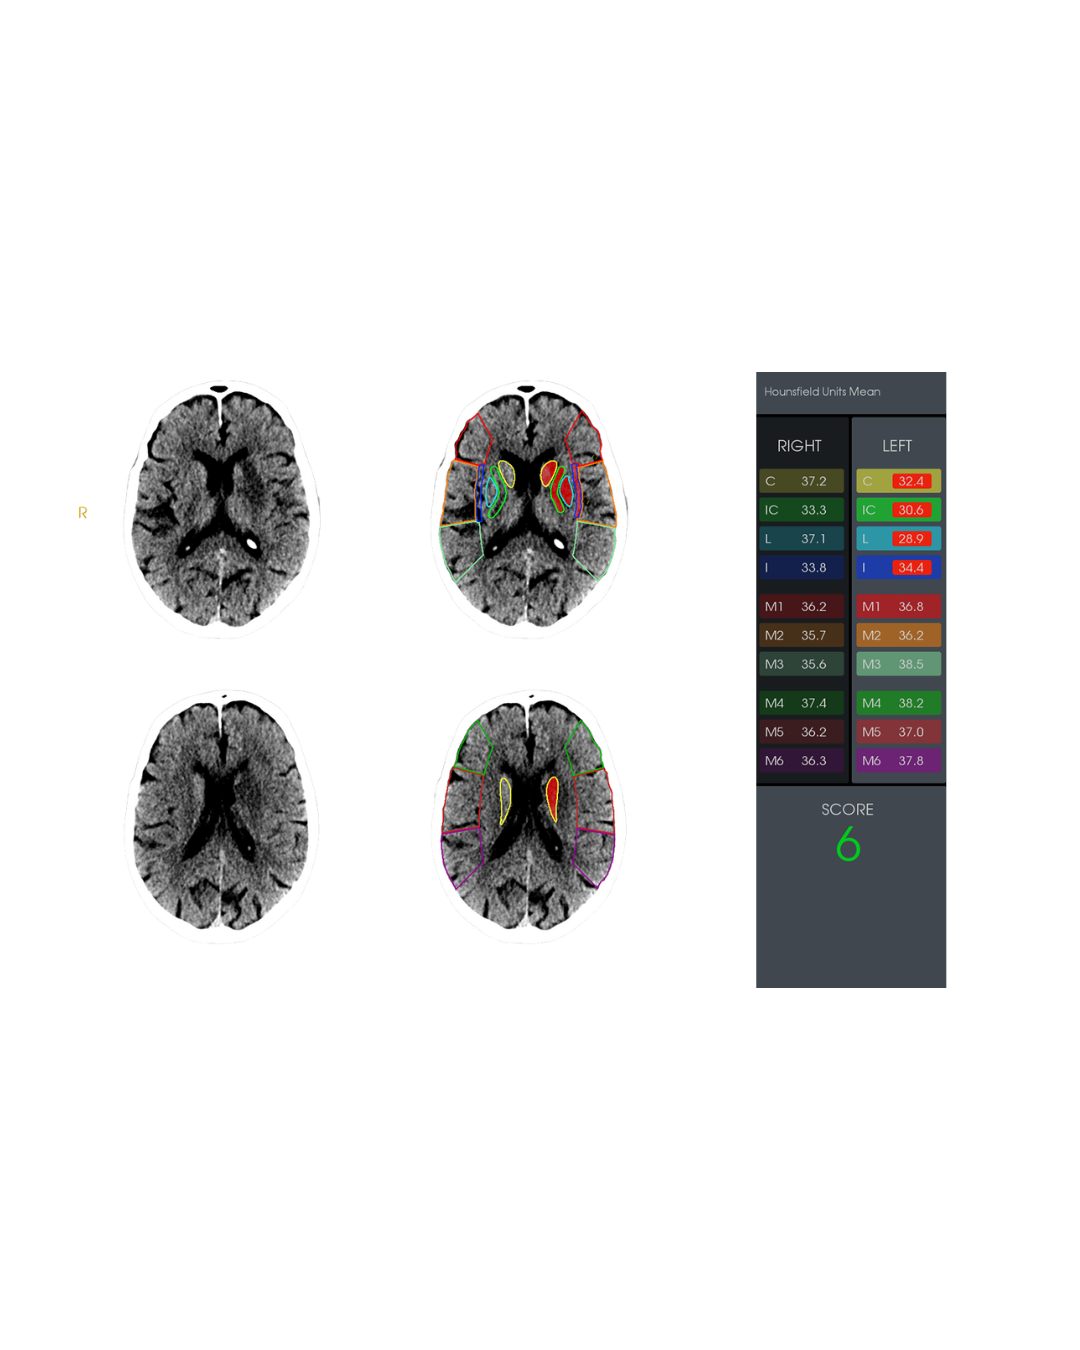

Advanced visualization

Automate measurements, vessel segmentation, and 3D reconstructions.